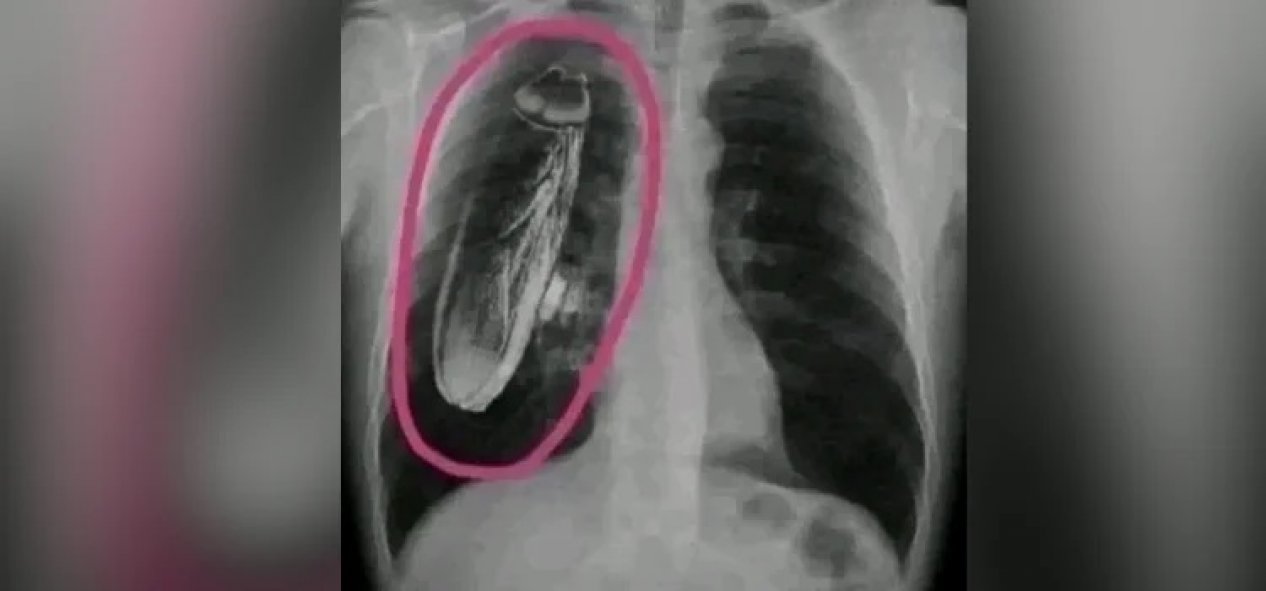

Sosyal medyada paylaşılan bir fotoğrafla Kenya’da bir hastanın göğüs röntgeninde hamam böceği görüldüğü öne sürüldü. İddiaya göre hasta, tedavi için Singapur'a kadar gelmiş ve Kenya’daki hastanenin yanıldığını, hamam böceğinin akciğerlerinde değil, röntgen cihazında olduğunu öğrenmiş.

İddiaya eklenen fotoğraf tersine görsel arama yöntemiyle arandığında, “hamam böceğinin” fotoğrafa sonradan eklendiği anlaşılıyor. Fotoğrafın aslı standart bir göğüs röntgeni.

İki görsel karşılaştırıldığında, böceğin sonradan eklendiği de görülüyor.

Anahtar kelimeler ile açık kaynaklardan yapılan aramalara göre de böyle bir olay kaydedilmemiş. Ayrıca, böcek görüntüsünün aktarıldığı gibi büyük olması bilime ve hayatın olağan akışına da aykırı.

Sonuç olarak görsel gerçeği yansıtmıyor, dijital müdahale ile oluşturuldu.